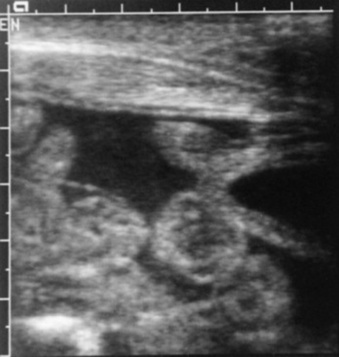

Ultrasonographic evaluation of the foal’s thorax can yield useful information in a variety of disease processes, including pleural effusion, such as hemothorax or pleuritis, bronchopneumonia, or abscessation. It is also the preferred method for diagnosing rib fracture or dislocation and congenital heart disease and thus is often a useful technique to differentiate cardiac and pulmonary causes of hypoxemia.61